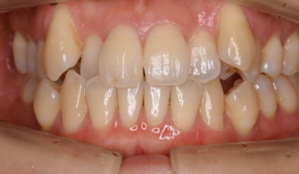

マウスピース型矯正装置(インビザライン)の症例

マウスピース型矯正装置(インビザライン)を使用した歯列矯正